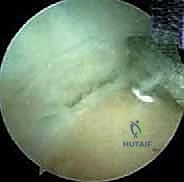

3. الاستكشاف التشخيصي بالمنظار:

يتم إدخال كاميرا المنظار عالية الدقة. يقوم الدكتور هطيف بإجراء فحص شامل وفحص ديناميكي للمفصل من الداخل، لتقييم حالة الغضاريف، البحث عن الأجسام الحرة (Loose bodies) الناتجة عن تفتت العظام، وتقييم حجم النتوءات العظمية في الناتئ المرفقي.

4. إزالة النتوءات العظمية (Osteophyte Excision):

هذه هي الخطوة الأكثر دقة وحساسية، وهنا تتجلى خبرة الأستاذ الدكتور محمد هطيف. باستخدام أدوات دقيقة (Burr)، يقوم بنحت وإزالة النتوءات العظمية الخلفية التي تسبب الانحشار.

تحذير جراحي هام: يؤكد الدكتور هطيف دائماً على قاعدة جراحية ذهبية في هذه العملية: "يجب إزالة العظام الزائدة فقط (النتوءات)، ويجب عدم المبالغة في إزالة جزء من العظم الأصلي للناتئ المرفقي". لماذا؟ لأن الإفراط في إزالة العظم سيؤدي إلى فقدان المفصل لاستقراره العظمي، مما يضع ضغطاً مضاعفاً ومميتاً على الرباط الجانبي الزندي (UCL)، وقد يؤدي إلى تمزقه بالكامل لاحقاً. هذه الدقة في تحديد "كمية العظم المزال" هي ما يميز الجراح الخبير عن غيره.